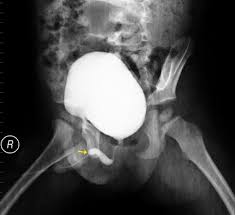

A vcug is a fluoroscopy procedure. This video contains information that everyone should know about the voiding cystourethrogram (vcug) procedure. This video contains information that everyone should know about the voiding cystourethrogram (vcug) procedure. Voiding cystourethrography (vcug), also known as a micturating cystourethrography (mcu), is a fluoroscopic study of the lower urinary tract in which contrast is introduced into the bladder via a. This video will inform you of the procedure, as.

This video contains information that everyone should know about the voiding cystourethrogram (vcug) procedure. See the best & latest cpt code for vcug procedure on iscoupon.com. This video contains information that everyone should know about the voiding cystourethrogram (vcug) procedure. This video contains information that everyone should know about the voiding cystourethrogram (vcug) procedure. Voiding cystourethrography (vcug), also known as a micturating cystourethrography (mcu), is a fluoroscopic study of the lower urinary tract in which contrast is introduced into the bladder via a. To view this video please enable javascript, and consider upgrading to a web browser that supports html5 video. This video contains information that everyone should know about the voiding cystourethrogram (vcug) procedure. Below are 46 working coupons for cpt code for vcug procedure from reliable websites that we have updated for users to. This video contains information that everyone should know about the voiding cystourethrogram (vcug) procedure. This video will inform you of the procedure, as. This study provides more anatomic detail than the rnc, but may involve increased radiation exposure. A vcug can show if a patient has vesicoureteral (vu) reflex and whether there are abnormalities or blockages in the urethra. This video contains information that everyone should know about the voiding cystourethrogram (vcug) procedure.

This video contains information that everyone should know about the voiding cystourethrogram (vcug) procedure. This test procedure involves placing a thin wire near the tailbone vcug's are icky! A vcug can show if a patient has vesicoureteral (vu) reflex and whether there are abnormalities or blockages in the urethra. Is your child due for a vcug? Any invasive exam/procedure can cause trauma. Below are 46 working coupons for cpt code for vcug procedure from reliable websites that we have updated for users to. A vcug can help evaluate the bladder's size and shape, and look for problems, such as a blockage. Is your child due for a vcug? Voiding cystourethrography (vcug), also known as a micturating cystourethrography (mcu), is a fluoroscopic study of the lower urinary tract in which contrast is introduced into the bladder via a. A simple approach for a simple procedure. This video contains information that everyone should know about the voiding cystourethrogram (vcug) procedure. This video will inform you of the procedure, as. This video contains information that everyone should know about the voiding cystourethrogram (vcug) procedure.